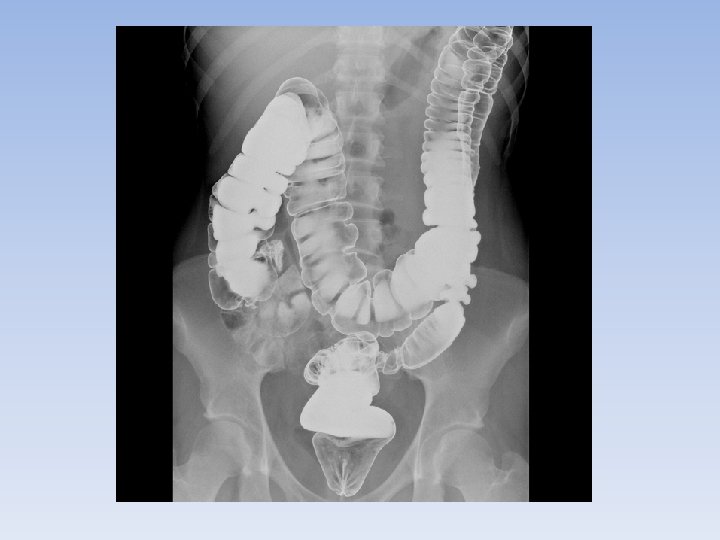

fluoroscopy • Technique using a continuous beam of x-rays to show the movement of organs like the stomach or intestines. • Patients usually have to ingest a contrast liquid to help the doctor see clearly (barium or iodide). • Used to study blood vessels of the heart and brain. These images are called angriograms. A dye can be injected into an artery in the groin, allowing doctors to see blood flow in the arteries and blood vessels. Can help prevent strokes or heart attacks.